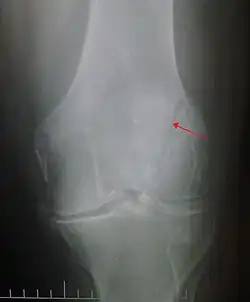

It typically results from a hard blow to the front of the knee or falling on the knee.[1]The patella can also be fractured indirectly. For example, a sudden contraction of the quadriceps muscle in the knee can pull apart the patella.[1]Diagnosis is based on symptoms and confirmed with X-rays.[3] In children an MRI may be required.[3]

Diagnosis is based on symptoms and confirmed with X-rays.[3] In children an MRI may be required.[3]

Some people have a normal bipartite patella or two-part patella which can appear as a fracture. The fragment is usually seen in the top outer corner of the patella and can be distinguished from a fracture by being present in both knees.[6]